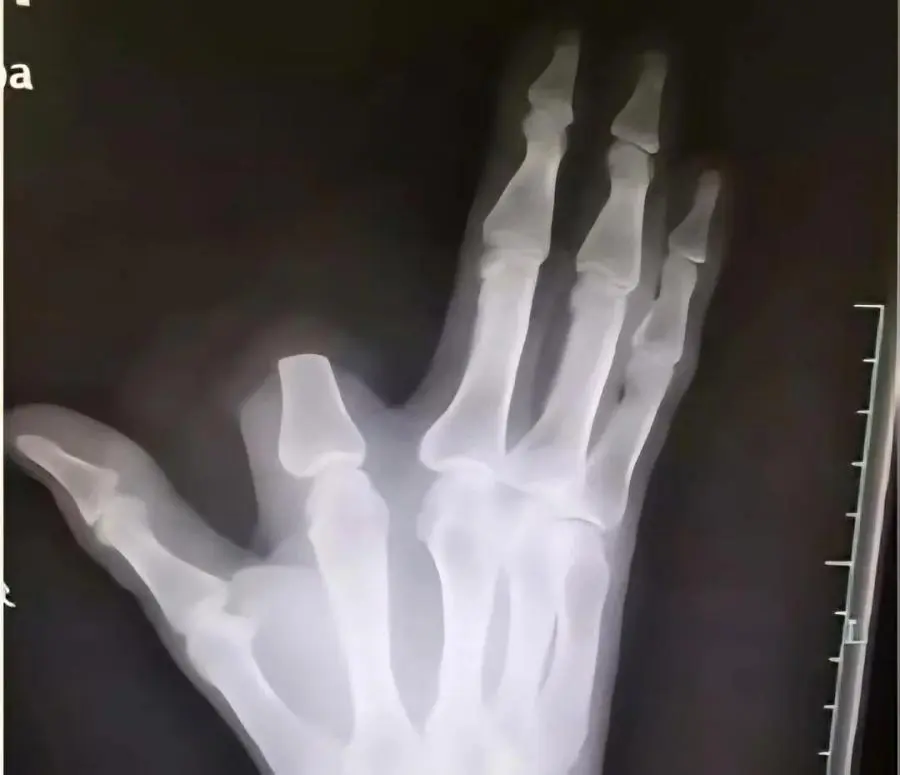

중국 저장성에 거주하는 60세 농부 장씨는

산에서 작업을 하던 중 독사에게 손가락을 물렸습니다.

그는 이 뱀이 물리면 다섯 걸음 안에 죽는다는 전설의 '오보사'라고 판단하고,

독이 퍼지는 것을 막기 위해 자신의 검지 손가락을 즉시 절단했습니다.

이후 그는 절단된 부위를 천으로 감싸고 80km 떨어진 항저우 시내 병원을 찾아갔습니다.

병원에 도착한 장 씨를 진찰한 의사들은 "손가락을 자를 필요가 전혀 없었다"고 말했습니다.

그가 물린 뱀은 독성이 있긴 하지만, 전설처럼 즉사할 정도의 치명적인 독은 아니었기 때문입니다.

장 씨는 병원 도착 당시 호흡 곤란이나 출혈 등 심각한 중독 증상을 보이지 않았으며,

상태가 매우 양호했습니다.

장 씨는 급하게 병원을 오느라 잘라낸 손가락을 산에 그대로 두고 왔습니다.

이 때문에 의료진은 그의 손가락을 다시 붙여줄 수 없었습니다.